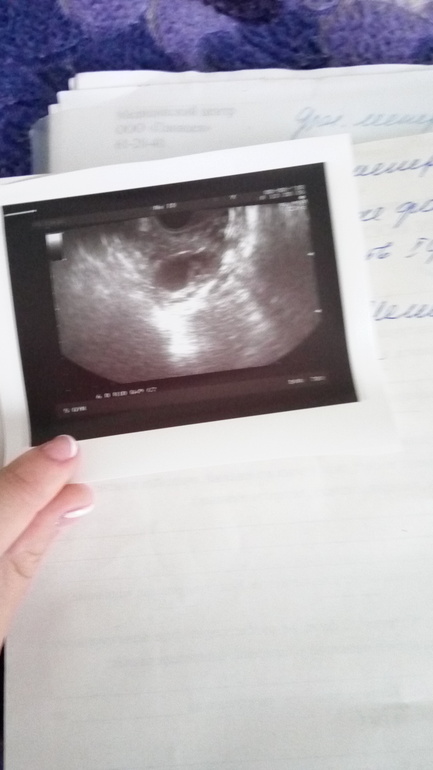

Фолликулометрия

На сегодняшний день вот такая картина 15 ДЦ,сейчас будем ставить укол,правда тревожит что опять в левом,но врач сказала что эндометрий хороший можно уколоть укол,буду надеяться что получится😳